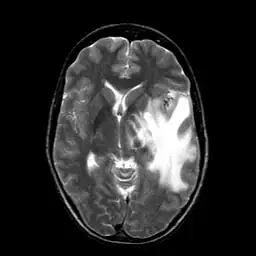

I am currently working on translating Matlab version active contour to OpenCV. It seems that OpenCV has its own version of active contour but deprecated then. I am curious about how different between this version with Matlab version. So I did a comparison experiment. Given a MRI brain image and an initial boundary , I applied both Matlab and OpenCV version active contour to segment the white matter in brain.

For both Matlab and OpenCV, I choose gradient(edge) method of active contour. I then labeled the results on the image. The red curve is initial boundary while the green curve is final boundary.